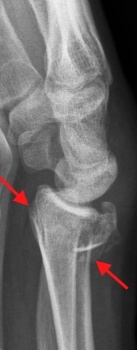

Die Röntgen-Aufnahme des Handgelenkes ist notwendig zur Bestätigung

der Diagnose Unterarm-Bruch und zur Beurteilung der Schwere der

Unterarm-Fraktur.

Dabei

wird das Handgelenk in mehreren Ebenen geröntgt. Besonders die

seitliche Darstellung des Unterarm-Bruches zeigt oft die erhebliche

Verschiebung (Dislokation)

Die Abb. links zeigt einen solchen

stark verschoben Bruch der Speiche. Hierbei ist die Bruchfläche ganz

typisch nach hinten (dorsal) weggekippt. Solche Speichen-Brüche

werden auch als Smith-Frakturen bezeichnet.